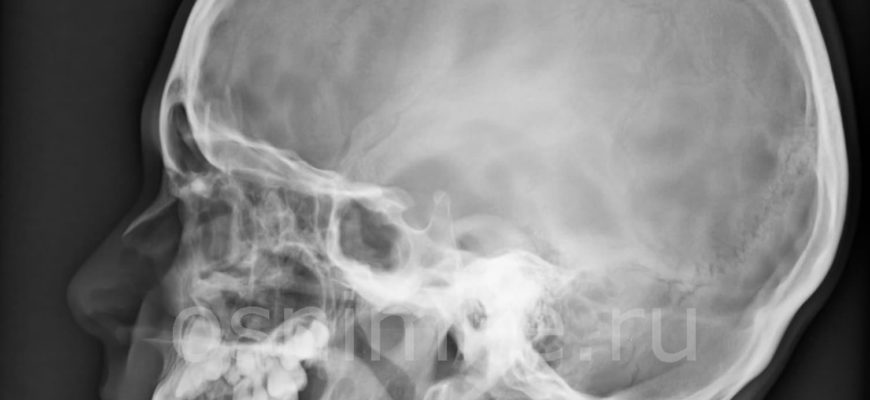

Визуализация черепа и мозга выполняется с помощью рентгеновских лучей. Когда они подвергаются воздействию тканей разной плотности, лучи по-разному поглощаются и выделяют разное излучение, которое записывается на пленку или в цифровом виде.

На полученном изображении плотные структуры выделены светлым цветом, оттенками белого и светло-серого. Так могут выглядеть нижняя челюсть, кости носа, скуловая кость, придатки височной кости и височно-нижнечелюстной сустав. Мягкие ткани и полости показаны черным цветом. Мельчайшие аномалии, такие как трещины, разрастания и переломы, видны при рентгенологическом исследовании костей черепа.